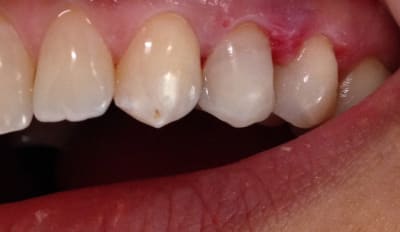

Alors comment traiteriez vous cette 24 asymptotique, qui présente un enorme délabrement sous gingival , notez que l'émail n'est plus soutenu par la dentine à aucun endroit ?

1ère séance remontées de la marche distale au compo flow + compo de restauration / réalisation d'un IDS , le tout sous digue bien sur (voir radio jointe , désolé à l'envers))

Je vous met les photos de la pose de ce matin, par contre désolé pour les puristes , mais photos faites avec un iphone....

Voici les photos toutes fraiches de ce matin.

Vos critiques sont bien sur les bienvenues je dois encore beaucoup m'améliorer sur les prises de teintes, et je m'y attelle en ce moment,, par contre en ce qui concerne la pérennité de la restauration…..ma patiente a sa dent bien vivante, aucun joint sous gingival , possibilité de réaliser une endo dans le futur sans détruire la restauration existante si besoin, possibilité re refaire un onlay dans quelques années si ça casse, toujours sur dent vivante…. bref la liste des avantages est très longue par rapport au classique endo-IC-CCM.